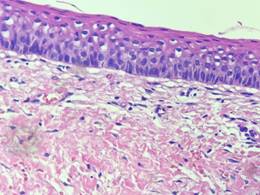

The histopathological examination was compatible with a dentigerous cyst. Given this result, the clinicians decided to wait for the lesion regression to minimize the likelihood of surgical damage of noble anatomical structures in the perilesional region (inferior alveolar neurovascular bundle and adjacent teeth).

Histopathological examination of the surgical specimen confirmed the initial diagnosis of dentigerous cyst (Figure 9).

Histologically, dentigerous cysts are characterized in most cases as a pathological cavity, lined by layered flat epithelium5,9. In some cases, there is a loose fibrous connective tissue capsule, islands or strands of odontogenic epithelium, dystrophic calcifications, and an inflammatory infiltrate of varying intensity9. This is compatible with the histopathological range of this case report.